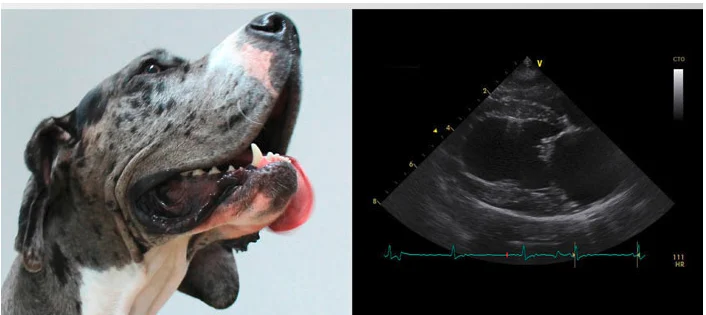

Praxis für KLEINTIER – KARDIOLOGIE – Dr. Nicole Sameluck – VetECHO stellt am Standort Krähenweg 5, 22459 Hamburg ein breit gefächertes und fachkundiges Leistungsspektrum im Bereich Tierarzt bereit. Ganz gleich, ob es sich um Haustierbesitzer, landwirtschaftliche Tierhaltungen oder neu entstehende Projekte der Nutztierhaltung handelt – Praxis für KLEINTIER – KARDIOLOGIE – Dr. Nicole Sameluck – VetECHO bietet in der gesamten Region verlässliche Unterstützung bei Untersuchungen, Behandlungen, Impfungen und vorbeugenden Gesundheitskonzepten. Dank der ausgeprägten regionalen Verankerung, der schnellen Reaktionswege und der persönlich abgestimmten Betreuung gehört Praxis für KLEINTIER – KARDIOLOGIE – Dr. Nicole Sameluck – VetECHO zu den meistgeschätzten tiermedizinischen Anlaufstellen der Umgebung.